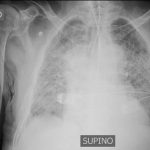

Il bilancio dei contagiati nelle ultime ore ha superato le 2.000 unità e, di questi, circa il 50% è ricoverato in ospedale. Sono un centinaio invece quelli che hanno bisogno di un posto letto in Terapia Intensiva.